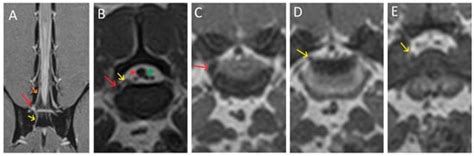

Conjoined Lumbosacral (L7-S1) Nerve Roots in a Dog